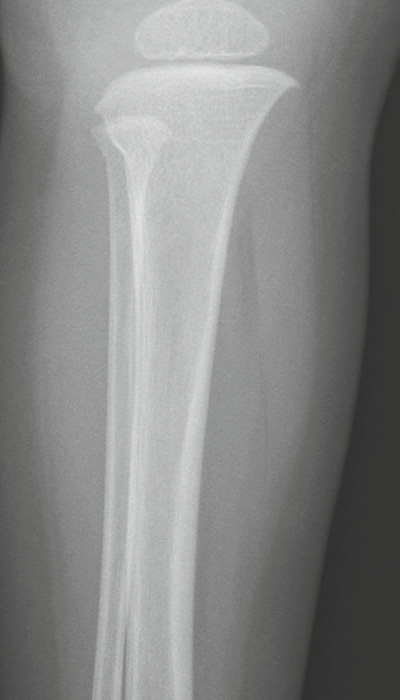

Toddler’s fracture

• When a child first begins to walk

• A nondisplaced oblique or spiral fracture of the midshaft

of the tibia

• Most children present with failure to continue to walk or refusal to bear weight on that extremity